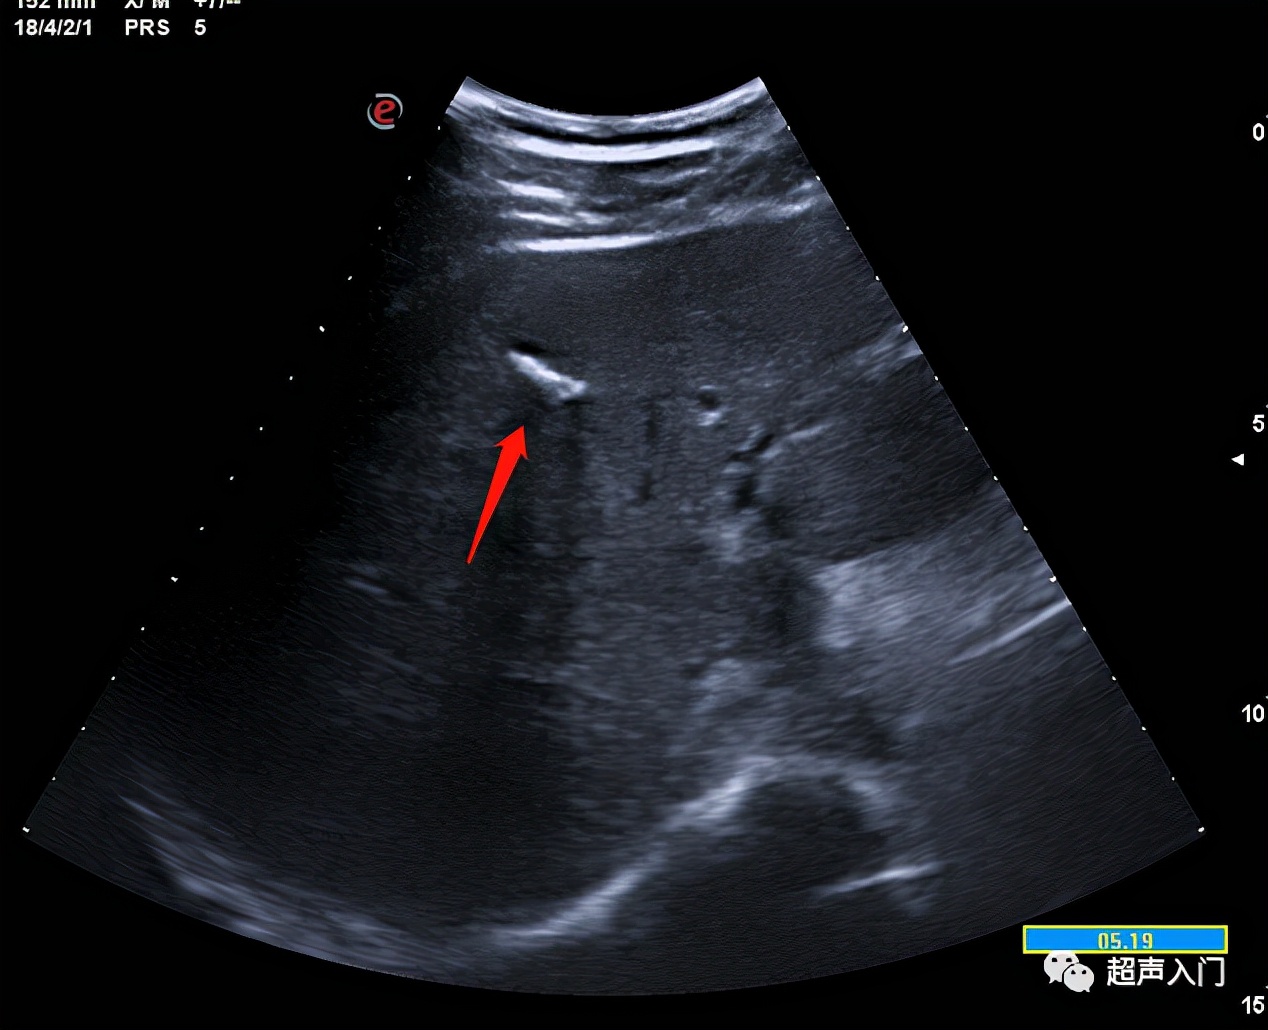

02 肝内钙化灶

(肝里的那个白条条)

04 肝内胆管结石

(肝里的白条条,注意和肝内钙化灶鉴别哦)